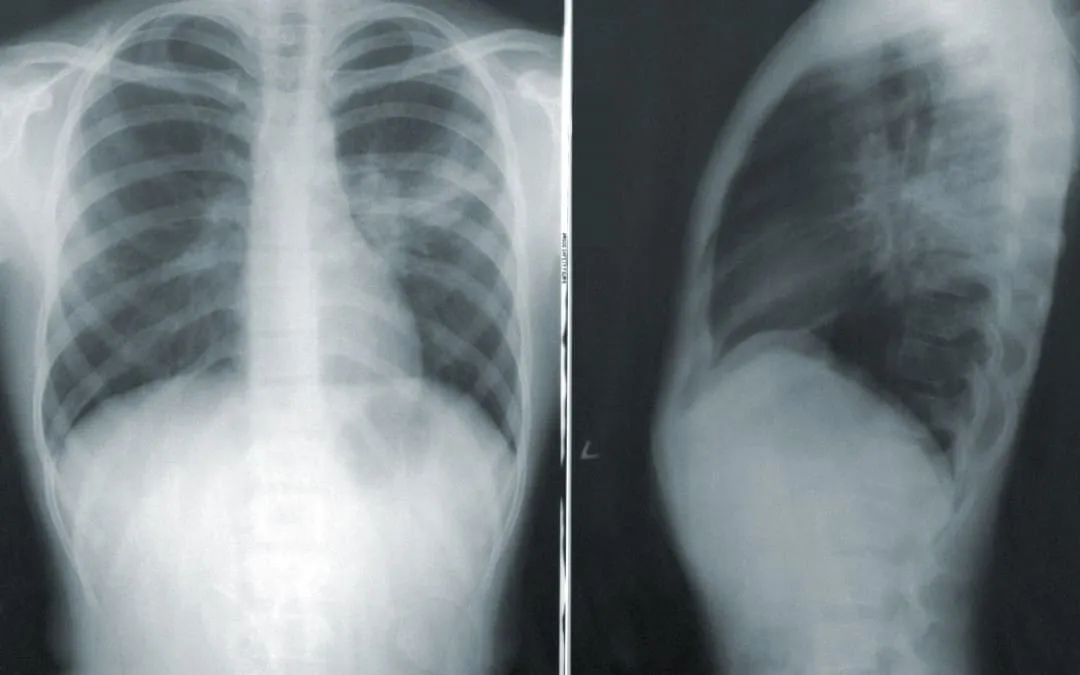

In order to pursue a claim for disability, we need to have medical evidence to document the severity of your respiratory disorder. This may include medical imaging such as x-rays or CT scans. It could include pulmonary function tests. Blood or other laboratory tests are frequently used along with prescriptions to document the severity of your disease and the steps taken to undergo treatment. A prescription for supplemental oxygen is often present in cases where your breathing is so severe, you need help with oxygen either part time or full time. You also may have a spirometry report, which provides your FEV1 value. FEV1 tracks the forced expiatory volume in the first second of a forced expiratory maneuver. Whatever medical evidence you may have, be sure to bring it with you when you meet us for a consultation. We may also send you back to your doctor with a residual functional capacity questioner for your doctor to complete so that we have a medical opinion of your limitations.